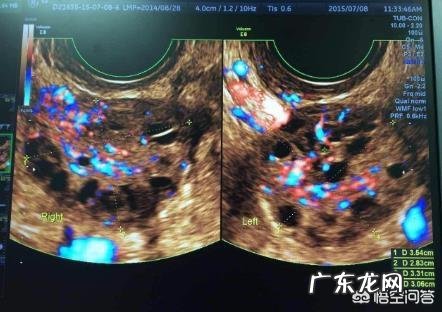

对于卵泡多大才算成熟?因人而异!一般来说,成熟的卵泡直径大小约在18-25mm 。

我们除了可以从直径这个标志上面考察卵泡是否成熟,还可以从卵泡中的卵子是否有和精子结合的能力以及卵子中是否形成了单倍染色体卵细胞来考察卵泡是否成熟 。

4)B超监测,患者双侧卵巢明显增大,卵巢表面有数个凸出的囊状卵泡;